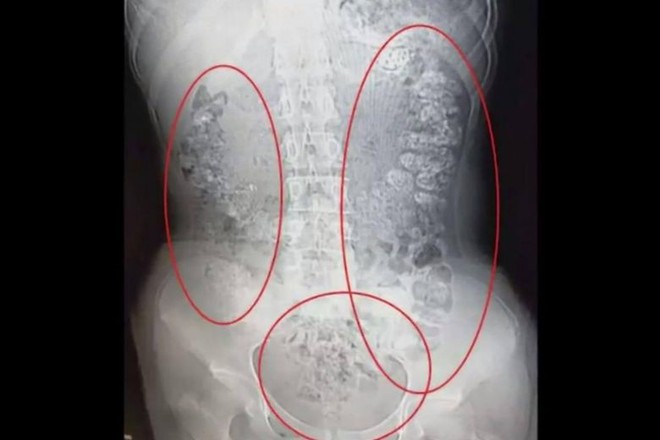

Các bác sĩ quyết định cho bệnh nhân chụp CT để tìm ra nguyên nhân. Kết quả cho thấy, trong ruột già dày đặc những dị vật hình cầu tối màu. Từ đại tràng lên, tràng ngang, tràng xuống, tràng sigma và hậu môn đều có những "khối cầu nhỏ" như thế.

(Ảnh: Weibo)